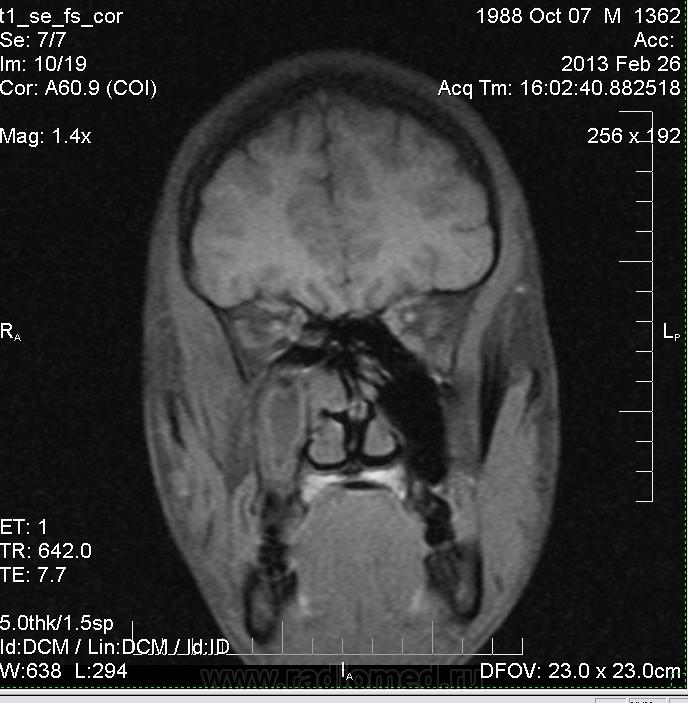

Правосторонний гайморит, фронтит, этмоэдит в фазе выпота. Киста ли это в верхне-медиальных отделах правой в/ч пазухи?

В мае удаляли зуб справа. Беспокоят гнойные выделения из полости носа. На ортопонтограмме со слов пациента без патологии. В области альвеолярного отростка верхней челюсти  справа в области коренных зубов визуализируется зона отека? деструкции?

У товарища похоже, что и фронтит и гайморит справа. Слева утолщенная слизистая. А словам, что на орто норма, можете не верить.

А может быть это аспиргиллема в правой в/ч пазухе?